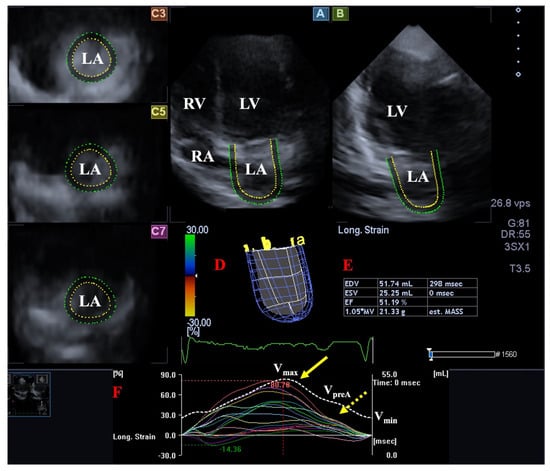

- Nemes, A.; Piros, G.Á.; Domsik, P.; Kalapos, A.; Forster, T. Left Atrial Volumetric and Strain Analysis by Three-Dimensional Speckle-Tracking Echocardiography in Noncompaction Cardiomyopathy: Results from the MAGYAR-Path Study. Hell. J. Cardiol. 2016, 57, 23–29. [Google Scholar] [CrossRef]

- Nemes, A.; Hausinger, P.; Kalapos, A.; Domsik, P.; Forster, T. Alternative ways to assess left atrial function in noncompaction cardiomyopathy by three-dimensional speckle-tracking echocardiography: (a case from the MAGYAR-Path study). Int. J. Cardiol. 2012, 158, 105–107. [Google Scholar] [CrossRef]

| LA emptying fractions were smaller and certain peak global LA strains were reduced. | [20] * | 12 | |